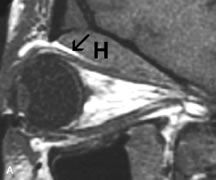

PATIENT PREPARATION Before MRI is performed, patients must be screened and prepared to avoid the potential hazards associated with the strong magnetic field. Patients who have ferrous aneurysm clips or cardiac pacemakers, who depend on life-support equipment, or who retain a possible metallic intraocular foreign body are not candidates for this imaging modality. MRI cannot be performed on obese patients who cannot fit into the bore of the magnet. Patients who are claustrophobic may not tolerate a prolonged period of study within the confines of the magnet, whereas others might do well if given a mild sedative. All worn metallic objects (e.g., necklaces, watches) should be taken off, credit cards set aside, and eye makeup removed before entering the room containing the magnet.5,20,34,35,36 NORMAL ORBITAL ANATOMY T1-weighted images provide the best anatomic details of the orbit because they display superior contrast resolution between normal structures (see Fig. 8). The vitreous has a long T1, resulting in an intermediate signal similar to brain, whereas the crystalline lens and sclera appear dark because of a longer T1 and short T2. The extraocular muscles, like all skeletal muscles, demonstrate a moderately long T1 and short T2 and highly contrast with the intense signal of the surrounding orbital fat (adipose tissue has an extremely short T1). The lacrimal glands appear as mottled areas of reduced intensity of the signal from the orbital fat in the lacrimal fossa. The optic nerves are seen with the same signal intensity as brain white matter and are hypointense relative to the orbital fat because their Tl is longer than the Tl of fat but shorter than the Tl of water. Cortical bone is not well delineated because it contains little free water, yielding minimal signal in MRI, and thus appears dark on all pulse sequences. This feature explains why MR images of the orbital apex and intracanalicular portion of the optic nerves are superior to comparable CT scans. Partial volume averaging of the bones in these regions obscures soft tissue details on CT images, whereas MRI reveals the signals only from the soft tissue structures with no cortical bone input. Bone marrow, on the other hand, is seen as a relatively intense signal because of its high fat content (see Fig. 8).37,38 T2-weighted pulse sequences are not ideal for imaging normal anatomy; however, they are particularly useful in revealing pathologic conditions (see Fig. 9). T2-weighted studies are most easily recognized by a bright vitreous signal. ORBITAL DISEASES Vascular Lesions Cavernous hemangiomas appear as well-circumscribed, smooth, usually intraconal masses that are isointense to muscle on T1-weighted images and hyperintense on T2-weighted images (Fig. 12). Patchy early enhancement is typically followed by diffuse, more homogeneous enhancement.39 The internal architecture of the mass, including septation and internal vasculature, may often be appreciated with high-quality orbital imaging.40 Lymphangiomas consist of ectatic vascular channels within a connective tissue stoma with varying degrees of lymphoid cellularity. On MRI, these tumors are typically poorly circumscribed, multicompartmental, and heterogeneous, often showing cystic dilations with fluid levels (Fig. 13). The signal characteristics within lymphangiomas vary considerably, reflecting cystic and solid components and the varying paramagnetic characteristics of blood at different stages of degradation.40–42 Acute hemorrhage appears hypointense on both T1- and T2-weighted formats. Methemoglobin present in subacute hemorrhage (3 to 14 days) leads to hyperintense signal on both T1- and T2-weighted images.41 A small percentage of lymphangiomas appear radiologically indistinct from orbital cavernous hemangiomas.43 Orbital varices are venous malformations that expand with increased systemic venous pressure, such as with Valsalva maneuvers. Because rapid acquisition of images during a Valsalva maneuver is important in imaging such a lesion, conventional or spiral CT is currently the modality of choice.44 MRI is an excellent modality for demonstrating enlargement of the cavernous sinus and dilation of the superior ophthalmic vein in patients with high-flow carotid-cavernous fistulas (Fig. 14).37MRA may be helpful in the evaluation of the venous outflow pattern. The rapidly flowing blood in these vascular structures carries the excited protons out of the section before they can be imaged, resulting in their dark appearance.5 In low-flow dural arteriovenous malformations, MRA may help define the arterial feeding vessels.45 Neural Lesions MRI is more effective than CT in delineating the intracranial optic nerves, chiasm, and optic tracts and, for this reason, is the preferred imaging modality in the evaluation of optic nerve disorders. The spatial relationships and image contrast of the orbital tissues with intraorbital optic nerve tumors is comparable between the two imaging modalities. The normal nerve is isointense to brain and appears enlarged and kinked owing to infiltration of an optic nerve glioma on T1-weighted images. Gliomas appear hyperintense on T2-weighted images and may be heterogeneous owing to cystic areas within the tumor. Contrast enhancement is variable.46 Intraorbital and intracranial optic nerve sheath meningiomas are usually isointense to cortical gray matter on Tl-weighted images and remain isointense on proton density studies (Fig. 15). Gd-DTPA is useful in delineating the intracranial extension of optic nerve meningiomas.7,47 The hyperostosis of bone and calcification associated with meningiomas are not demonstrated as well on MRI studies as on CT scans.20,37 Gd-DTPA–enhanced MRI also appears promising in the study of the permeability of the blood–brain barrier in selected optic neuropathies.22,48 MRI may reveal an enlarged optic nerve and some degree of contrast enhancement in cases of optic neuritis.49 Muscle Disorders Extraocular muscle enlargement in patients with thyroid-associated orbitopathy is demonstrated equally well with CT and MRI studies. However, the superior tissue contrast on MR images reveals better details of the relationships of the optic nerve to the thickened muscles at the orbital apex (Fig. 16).50 In addition, MRI may be able to differentiate between muscles that are enlarged as a result of edema and active inflammation and those enlarged because of fibrosis by their T2 relaxation times.21 Quantitative MRI was not found to be accurate in predicting the success of low-dose orbital irradiation.51 However, a muscular index relating the diameters of the rectus muscles to the bony orbital dimensions was useful in predicting optic nerve compression.52 MRI is also effective in imaging orbital tumors of mesenchymal origin, such as rhabdomyosarcoma, particularly in the assessment of extension into the anterior and middle cranial fossae (Fig. 17).37 The lack of any pathognomonic radiologic features necessitates rapid orbital biopsy when rhabdomyosarcoma is suspected. Osseous Lesions In general, CT is the imaging modality of choice when details of quantity and quality of bone are needed; however, abnormalities of bones can be detected indirectly by MRI. Cortical bone appears black (signal void) on MR images because of its low proton density and free-water content. The absence or discontinuity of the signal void of the orbital walls may represent bony destruction or fracture. Hyperostosis associated with prostate metastases or meningioma is visualized as areas of black smudging.50,53 Diseases in which the bone is replaced by pathologic tissues with a high free-water content, such as fibrous dysplasia, are well demonstrated on MRI. An intermediate signal intensity on T1-weighted images and hypointense signal on T2-weighted images is representative of fibrous dysplasia. Enhancement on post–Gd-DTPA MR scans is seen and is more evident in areas that are less mineralized.54 Cystic Lesions Dermoid cysts appear as rounded, well-defined lesions typically contiguous with an orbital bony suture. The high-intensity signal on T1-weighted images is attributed to the sebaceous-produced lipid contents (Fig. 18).31,50 Mucoceles may demonstrate a hypointense or hyperintense signal on MR images, depending on the concentration of proteinaceous or inflammatory fluid components. The integrity of the bony walls of the expanded sinus cavities cannot be assessed on MR as well as by CT.37,50,55,56 A high-signal intensity on Tl- and T2-weighted images is characteristic of orbital chronic hematic cysts because of the blood-breakdown products within the cysts.57 Trauma Although soft tissue relationships are usually better demonstrated on MRI, the evaluation of craniofacial bony trauma is preferable with CT. For example, prolapse of orbital fat through a fracture site and hemorrhage of adjacent tissues are demonstrated in an MR image, but the actual fractured bone is not imaged. Three-dimensional MRI of the orbit in subacute trauma has been described,58 although its precise role is not currently established. MRI has been suggested to be superior to CT in detecting intraorbital wooden foreign bodies.59,60 In a series of penetrating orbital injuries with organic foreign bodies, however, MRI was able to identify the foreign body in only four of seven cases.61 With an in vitro model for wood foreign body, McGuckin and colleagues concluded that CT was the imaging modality of choice.62 A careful history and, in selected cases, plain films to rule out a metallic foreign body are crucial before MRI is considered in patients with periocular trauma. MRI is particularly helpful in the detection and characterization of subperiosteal hematomas of the orbit (Fig. 19). They are most commonly seen in the subperiosteal space of the superior orbit as well-defined masses following a traumatic injury. The signal intensity varies depending on the acute, subacute, or chronic nature of the hematoma, based on the stage of blood degradation. Fresh hemorrhages are hypointense on T1-weighted images and hyperintense on T2 images. Hematomas that are 1 to 7 days old are hypointense on both T1- and T2-weighted images. T1-weighted images of hematomas more than a week old are hyperintense due to the oxidation of deoxyhemoglobin to methemoglobin, whereas the T2 images remain hypointense.63 Metastatic Tumors Breast carcinoma metastatic to the orbit has been demonstrated to be hypointense to the surrounding orbital fat on T1-weighted studies and hyperintense on T2-weighted images and has an affinity to the extraocular muscles (Fig. 20).50,64 The MRI characteristics of prostate carcinoma metastatic to the orbit have been described as involving the greater and lesser wing of the sphenoid, orbital roof, and optic canal. Diffuse bone hypertrophy with isointense or slightly hyperintense tissue on T1-weighted images represents the osteoblastic carcinomatous bone infiltration. Contrast enhancement is variable on T1-weighted and fat-suppressed images.65 Most other metastatic tumors also have a lower intensity signal on T1-weighted images and appear to displace or infiltrate normal orbital structures; however, their signal characteristics are variable on T2-weighted MR images.66 Many metastatic tumors demonstrate bright contrast enhancement with Gd-DTPA. Infectious Disorders MRI findings of preseptal and orbital cellulitis typically include increased signal intensities on T2-weighted images of the eyelids and orbital fat, respectively, due to the increased water content of the tissues. Since most cases of bacterial orbital cellulitis are associated with paranasal sinusitis, hyperintense signals of the affected sinuses may also be found on T2-weighted images as well as enhancement of polyps and granulation tissue on postgadolinium T1-weighted MR images. Subperiosteal abscess formation may occur due to contiguous spread of infection from the paranasal sinuses and appear on MRI as an area of intermediate signal on T1-weighted and proton-weighted MR images. The abscess may appear slightly hyperintense compared with muscle on T2-weighted scans with the necrotic contents having the greatest intensity.67 MRI and MRV are more sensitive than CT in revealing cavernous sinus thrombosis. Engorgement of the cavernous sinus, extraocular muscles, and ophthalmic veins is seen with hyperintensity of the thrombosed sinuses evident on all pulse sequences. The enlarged, thrombosed superior ophthalmic vein appears less hypointense than the normal contralateral ophthalmic vein, and hyperintensity within the lumen of the vessel may be seen on T1- and T2-weighted MR images.68 Inflammatory and Lymphoproliferative Lesions Inflammatory conditions of the orbit, both idiopathic (inflammatory pseudotumor) and those of known causes, have been found to be hypointense to fat and isointense to muscle on Tl-weighted studies and isointense or slightly hyperintense to fat on T2-weighted images (Fig. 21).50,64,69 The more fibrous or sclerosing varieties have less signal intensity on T2-weighted images. Marked enhancement is seen in pseudotumor infiltrates after gadolinium administration.70 The same signal characteristics are demonstrated in patients with Tolosa-Hunt syndrome, with mass lesions seen in the cavernous sinuses and orbital apices.71 Lymphomas have MRI characteristics similar to those of inflammatory lesions in that they are hypointense to fat and isointense to muscle on T1-weighted images (Fig. 22). They may appear hyperintense to fat on T2-weighted images, perhaps owing to less fibrosis than that seen in orbital inflammatory pseudotumor, although this is not a consistent finding.31,50,66 Lymphoid tumors typically enhance moderately after contrast injection. Unfortunately, studies have shown that tumor density and homogeneity are similar between inflammatory and malignant orbital infiltrates, and MRI cannot differentiate these lesions.72,73 Lacrimal Gland Tumors Lacrimal gland lesions present special problems in diagnosis and management. Pleomorphic adenoma (benign mixed tumor) should not be biopsied, but rather excised in toto. On the other hand, for lymphoma and inflammatory infiltrates, incisional biopsy is more appropriate than complete excision of the lacrimal gland. Thus, preoperative clinical and radiologic evaluation are especially crucial in planning appropriate surgical management. Pleomorphic adenomas demonstrate long T1 and T2 signal characteristics. They may show heterogeneity on T2-weighted images74 and moderate to marked enhancement with contrast.75 Signal characteristics of adenoid cystic carcinoma include hypointensity to fat on T1-weighted images, hyperintensity to fat with increased T2 weighting, and isointensity to fat on proton density-weighted studies (Fig. 23).31,75 Secondary bony alterations of the lacrimal fossa associated with lacrimal gland tumors, such as remodeling (benign mixed tumor) or destruction (adenoid cystic carcinoma), are seen indirectly on MR images; however, bone windows on CT scans provide better delineation of these changes. In contrast to the round or globular appearance of benign or malignant epithelial tumors of the lacrimal gland, lymphoproliferative tumors usually appear to be molding or draping onto the globe and the surrounding bony orbit. LACRIMAL DRAINAGE SYSTEM DISORDERS MRI with surface coils provides excellent spatial resolution and tissue-specific signal intensities of the lacrimal drainage system. These parameters have been found useful to more accurately demonstrate the extent of lesions in the lacrimal sac and differentiate long-standing mucoceles from solid tumors than CT.76 Physiologic studies in patients with tearing disorders now include MR dacryocystography, in which Gd-DTPA is either placed topically in the conjunctival fornix or injected by cannulation into the lacrimal sac. They provide a detailed morphologic and functional analysis of the lacrimal excretory system; however, they are no more sensitive than digital-subtraction dacryocystography or CT dacryocystography.77–79 INTRAOCULAR TUMORS On MRI, uveal melanomas have a typical appearance that helps to differentiate them from other primary and secondary intraocular tumors as well as choroidal detachments. Pigmented melanomas are hyperintense on Tl-weighted images, hypointense on T2-weighted studies, and hyperintense on proton density–weighted examinations (Fig. 24).30,31,50,80–82 These signal characteristics have been attributed to the paramagnetic properties of melanin because of stable free radicals that shorten the T1 and T2 relaxation times. Moderate enhancement is seen on postgadolinium T2-weighted images. Gadolinium-enhanced T1-weighted images are particularly sensitive in detecting choroidal melanomas.83 MRI may be less sensitive in detecting extrascleral extension of tumor than echography performed by an experienced ultrasonographer.84 Tumors metastatic to the choroid are hyperintense on T1- and T2-weighted images.24 The signal characteristics, however, may be similar to those seen with choroidal melanoma. Choroidal hemangiomas, on the other hand, have an intermediate signal on T1-weighted sequences and become hyperintense on T2-weighted images50 as well as proton density–weighted images.81 Retinoblastomas display moderate signal intensity on T1-weighted studies and a low signal on T2-weighted images.31,80,85 Calcification can be easily detected by CT and ocular ultrasonography but is not imaged by MRI.25,50 The presence of optic nerve involvement is best evaluated by MRI. ACQUIRED ANOPHTHALMIA When an eye is removed owing to tumor or trauma, an implant is typically placed in the intraconal space. MRI may be useful in defining the size, shape, and position of such orbital implants.86 Porous hydroxyapatite or polyethylene implants are preferred by many surgeons performing enucleation or evisceration. A porous implant offers the possibility of supporting a motility coupling peg to increase the movement of the overlying prosthesis. MRI with contrast is used by some surgeons to evaluate the degree of fibrovascular ingrowth in hydroxyapatite87 and porous polyethylene88 implants prior to motility peg placement. |